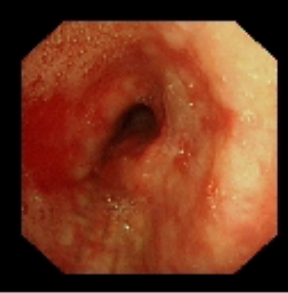

术前气管重度狭窄